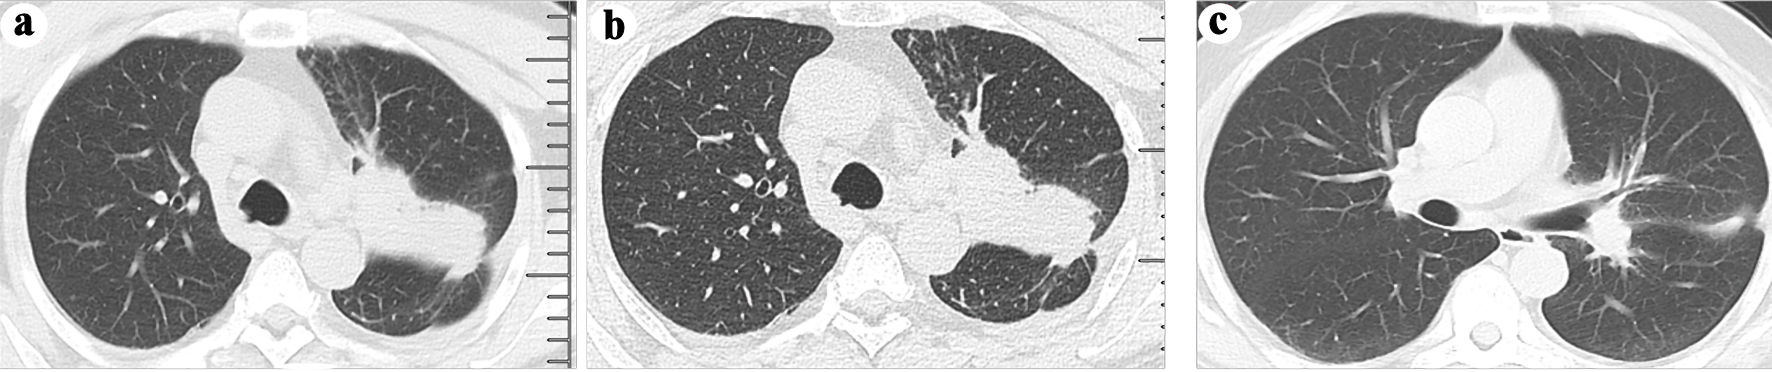

Then we arranged a magnetic resonance imaging (MRI) to examine the thigh, hip joint, and the spine. The results of thigh and hip joint revealed aggressive cortical destruction of left proximal femur, with an adjacent extraosseous soft tissue mass. MRI results also showed possible multiple bone metastases to the right proximal femur, bilateral ilium, bilateral ischium, bilateral pubis, and spine (Fig. 1a-d). Accidentally, the patient develops spontaneous fracture of left proximal femur, which could not enable a computed tomography (CT) scan due to unbearable pain. Therefore, an ultrasound-guided needle biopsy of the mass was conducted, and lung adenocarcinoma was diagnosed based on pathologic examination. In order to facilitate further examination and treatment, we applied external fixation to temporarily fix the displaced pathological fracture. Then, we conducted chest CT, with results showing a lesion at the left upper lobe (Fig. 2a, b), which is finally revealed as stage IV adenocarcinoma (Fig. 3a-c). Then the patient was transferred to the oncology department for further management, where mutational analysis of the tumor revealed an EGFR exon 19 deletions mutation, and the patient then received osimertinib, an EGFR-tyrosine kinase inhibitor (TKI).

![]() Click for large image | Figure 2. (a) A neoplasm in the left upper lobe was observed on a computed tomography (CT) scan. (b) The presence of a neoplasm in the left lung was confirmed through an enhanced CT scan. (c) A follow-up CT scan at 3 months after osimertinib administration revealed shrinkage of the neoplasm in the left upper lobe. |

At the 3-month follow-up, he exhibited a favorable response to osimertinib without any further deterioration of his condition (Fig. 2c). Additionally, he underwent left proximal femoral replacement at a local hospital. At the 6-month follow-up, he achieved disease stability and regained the ability to ambulate freely.